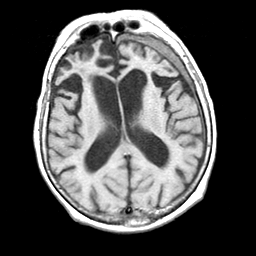

Pick's Disease, MR Study mr-t1 -- Slice #12

[Home][Help][Clinical] Slice 12